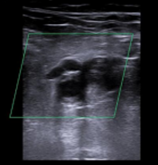

Hallazgos ecográficos

Ecografía clínica en el mismo momento de la consulta: vena poplítea derecha y vena safena derecha no compresibles imagen hipoecocicas sugestivas de tombo sugiere trombosis venosa profunda en territorio poplíteo. Se deriva a hospital.

Ecografía diagnóstica Doppler de confirmación en hospital: trombosis venosa profunda poplítea derecha.